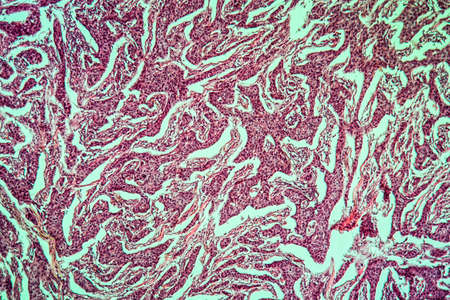

Breast cancer of the woman diseased tissue 100x